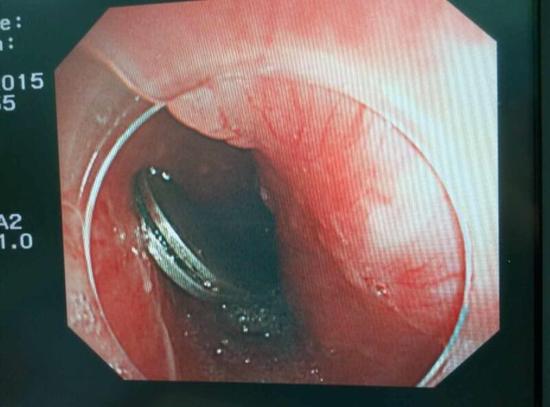

手術(shù)中,范醫(yī)生通過胃鏡準(zhǔn)確發(fā)現(xiàn)了胃里的鑷子。但讓他驚訝的是,在華先生胃底竟然還躺著三個(gè)被腐蝕了的打火機(jī),打火機(jī)的金屬部件都已經(jīng)不見了。

隨后,范醫(yī)生先用圈套器套取出了長(zhǎng)10厘米的鑷子,再一個(gè)一個(gè)地取出了打火機(jī)。整個(gè)取出過程小心謹(jǐn)慎而又一氣呵成,只用了不到10分鐘。

“真的是太危險(xiǎn)了。”范醫(yī)生表示,鑷子前端比較尖銳,一旦刺穿胃前壁,又有可能刺破肝臟,引發(fā)臟器受損和大出血。而打火機(jī)在胃內(nèi)酸性胃液腐蝕后,不 僅塑料外殼有毒,打火機(jī)內(nèi)的燃料一旦發(fā)生泄露會(huì)有灼傷胃腸道的危險(xiǎn)。打火機(jī)頭端還有尖銳金屬部件,若嵌頓或劃傷腸道會(huì)誘發(fā)腸梗阻、腸穿孔、消化道出血等嚴(yán) 重并發(fā)癥。